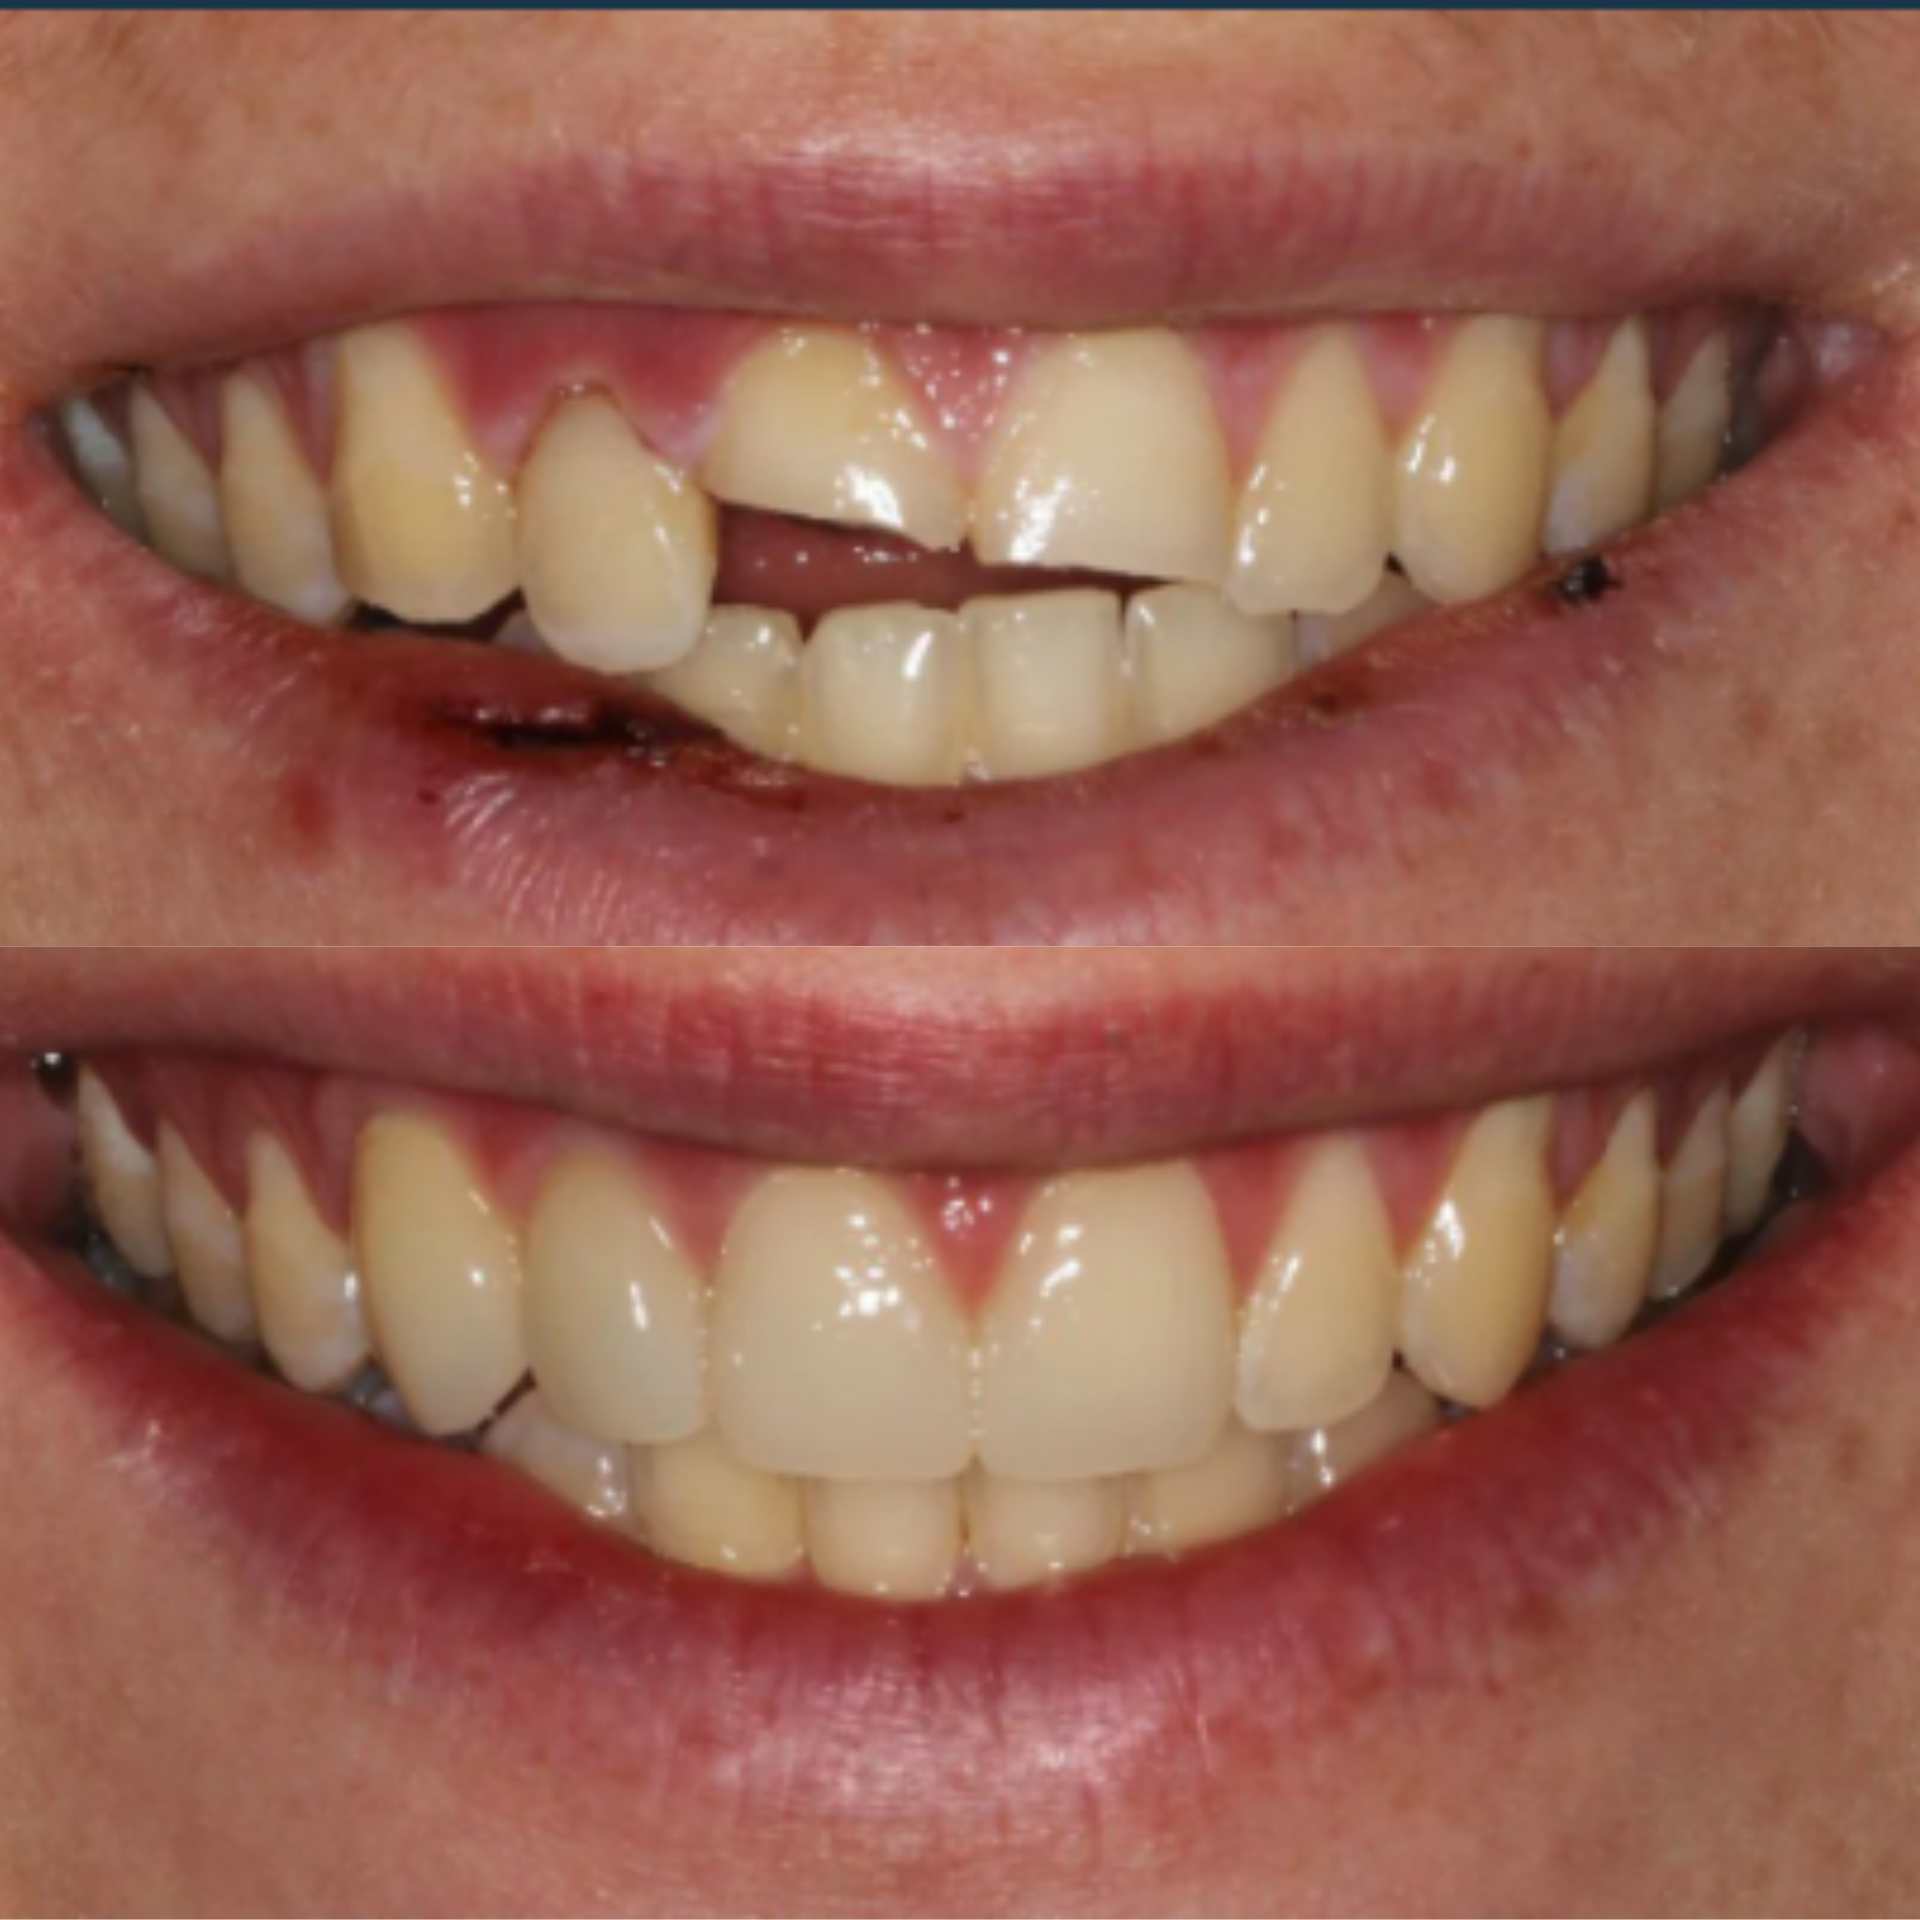

At Elite Dental Group, we provided emergency care that included root canal treatment on the upper central incisors. Dr. Satish Palayam performed an immediate implant placement for the right lateral incisor and completed a crown lengthening procedure on the palatal side of the right central incisor to support proper restoration. A provisional bridge was then placed to maintain both function and esthetics throughout the healing phase.

After a four month healing period, the final crowns were placed on the central incisors, and the implant for the right lateral incisor was successfully restored and finalized.